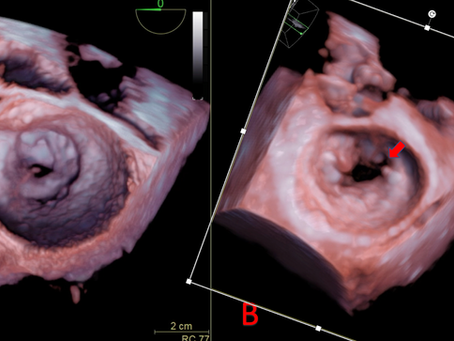

Respuesta al caso de la semana

¿Cuál de las imágenes es compatible con estenosis mitral reumática? La respuesta correcta es A. La imagen de la derecha (B) corresponde a...

ESTENOSIS MITRAL REUMÁTICA

En base a las siguientes imágenes responde la pregunta a continuación: